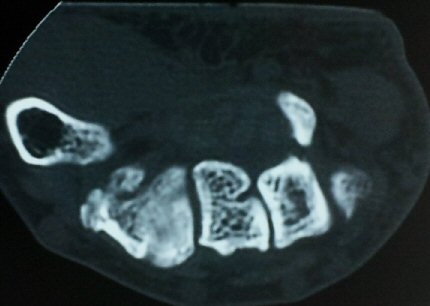

ÄÄÇ»ÅÍ ÃÔ¿µ»ó °¥°í¸®»À °¥°í¸® °ñÀýÀ» º¸ÀÓ(±×¸² 5, 6, 7).